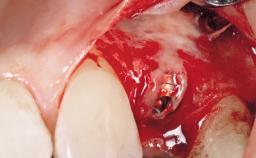

Immediate Flapless Placement of an Implant in a Maxillary Right Lateral Incisor Site

This 43-year-old male patient, a non-smoker, came to our practice because of a fracture of tooth 12 caused by a bicycle accident. Due to the combined para- and infrabony crown and root fracture, tooth extraction, and subsequent implant placement were suggested to the patient as the therapy of choice. The patient had high esthetic expectations with regard to the treatment outcome and asked for an immediate fixed provisional restoration. His individual esthetic risk profile summed up to a medium esthetic risk.